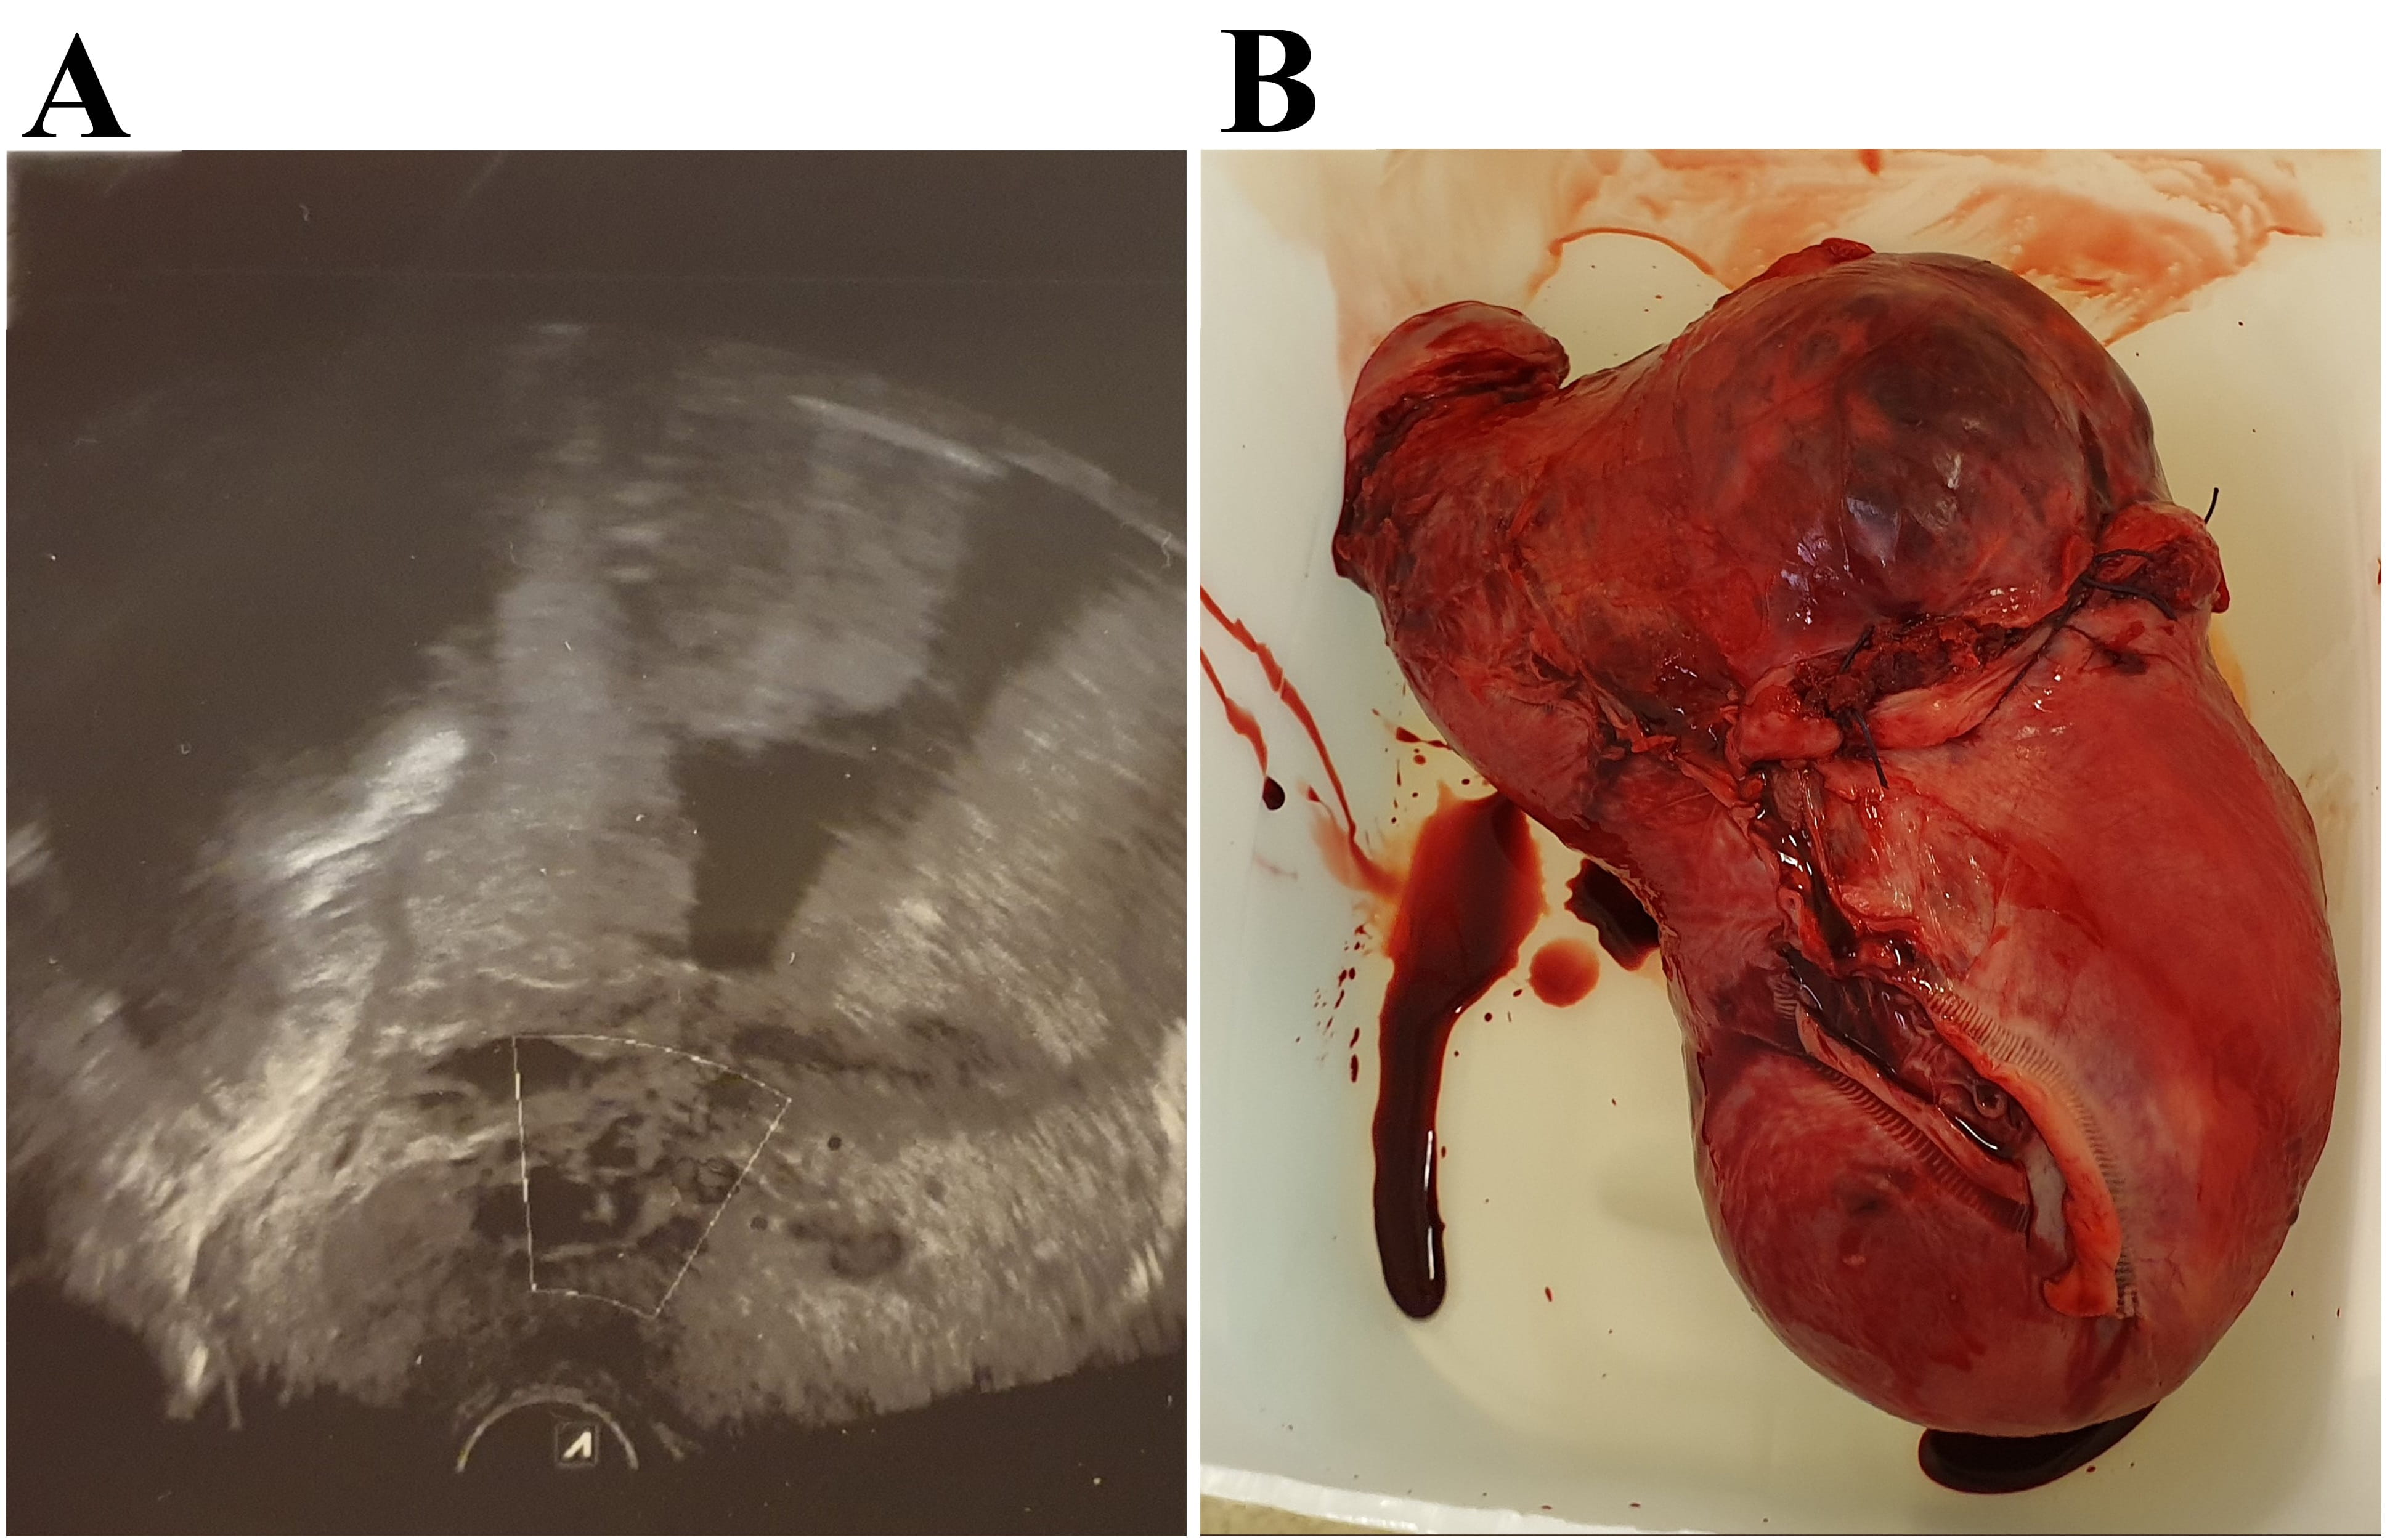

The second case included another woman, 41 years old (gravida 3). The patient’s first pregnancy finished with vacuum-assisted vaginal delivery; this child has severe mental disorders while the second child was delivered by planned CS. She was also a heavy smoker, and her pregnancy was additionally complicated by gestational diabetes mellitus, well-regulated with a diet. At 22 weeks of gestation, she was hospitalized due to the painless bleeding, placenta previa and placenta percreta were diagnosed by ultrasound and confirmed by MRI (Fig. 2). The ultrasound examination was obtained carefully due to the high risk of PAS. Imaging showed placenta previa completely covering the cervix and extending to the anterior wall of the uterus, there was presence of multiple vascular lacunae (a Swiss cheese appearance) irregular in shape, also the absence of the clear space between the placenta and the myometrium, existence of irregularity of the uterine serosa—bladder interface. The colour Doppler showed turbulent flow through the lacunae and outsized vessels.

Fig. 2.Preoperative 2D transvaginal ultrasound image and the uterus after a total hysterectomy. 2D transvaginal ultrasound showed the absence of placental-myometrial interface and the existence of multiple vascular intraplacental lacunae (A). Uterus with the placenta in situ after a total hysterectomy (B).

Few days later, the bleeding has stopped, and she was discharged. The second time, she was hospitalized due to preparation for planned caesarean delivery in 34 weeks of gestation. Corticosteroid therapy was administrated for foetal lung maturation. Both she and her husband were informed about the possible outcomes such as obstetric complications and they agreed to hysterectomy after baby was delivered. An elective CS was performed in the 35th week of pregnancy. After opening the abdominal wall by a Pfannenstiel relaparotomy, the inspection showed deep pelvis neovascularization with abnormal invasion of placenta tissue at the anterior uterine wall and rupturing of placental tissue throughout serosa, but there was no invasion to the adjacent organs. The transverse corporal hysterotomy was performed above the lower uterine segment and a healthy premature neonate weighing 2500 g was delivered. Also, in this case, the patient received tranexamic acid to minimize uterine bleeding during the surgery, total hysterectomy and bilateral salpingectomy with the placenta in situ was performed. The abdomen was inspected for haemorrhage; the surgery was finished by placing abdominal drain. Intraoperative allogeneic red blood cells (500 mL) and fresh frozen plasma (500 mL) were transfused. The puerpera was transferred to the intensive care unit and received additional 500 mL allogeneic red blood cells and 450 mL fresh frozen plasma. The patient was discharged on the 5th postoperative day. Intraoperative and histopathological findings confirmed the antenatal diagnosis of placenta percreta (Fig. 2). Both cases had a total hysterectomy; women refused to preserve fertility due to the high risk of complications. We did not use any adjunctive methods described in the literature, due to inability to perform those in our hospital.